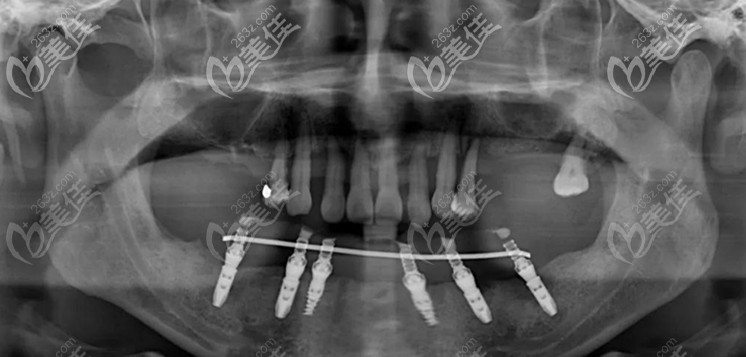

▲下頜的6顆即刻種植牙

第二次在進(jìn)行上半口的上頜穿翼板VIIV即刻種植技術(shù),整個手術(shù)進(jìn)行了2個多小時,在周院長和蔣院長的配合下,6顆植體都按照既定設(shè)計方案植入骨內(nèi)。

▲上半口兩顆傾斜的植體就是穿翼板種植技術(shù)

其中有2顆是高難度的穿翼板植體,避開了錯綜復(fù)雜的神經(jīng)血管,此技術(shù)不植骨、不等待、出血量少,突破了傳統(tǒng)種植牙對牙槽骨條件的限制。